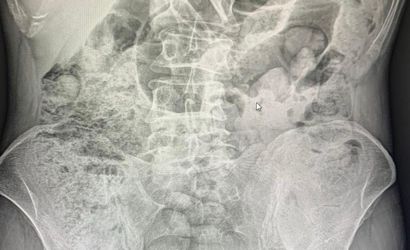

Siirt'te 4 zanlının midesinden çıkarılan 1 kilo 597 gram uyuşturucu madde, 10 gün süren hastane tedavisinin ardından cerrahi müdahale ile elde edildi. Tutuklanan zanlılar arasında 3 İran uyruklu kadın ve 1 erkek bulunuyor.

Siirt Emniyet Müdürlüğü Narkotik Suçlarla Mücadele Şube Müdürlüğü, 14 Aralık'ta Baykan Şehit Bünyamin Torgut Polis Uygulama Noktası'nda durdurduğu iki araçta, uyuşturucu madde taşımak için yutma yöntemini kullanan kişileri yakaladı. Yapılan incelemeler sonrasında, şüpheli şahısların midelerindeki uyuşturucu maddeler, 10 gün süren hastane süreci sonunda cerrahi yöntemle çıkarıldı.

Cerrahi Müdahale ile Elde Edilen Uyuşturucu

Midelerde toplamda 119 paket halinde 1 kilo 597 gram uyuşturucu madde tespit edildi. Zanlılar, çıkarıldıkları adli makamlarca tutuklanarak cezaevine gönderildi.

SİİRT’TE 4 ZANLININ MİDELERİNDEKİ 1 KİLO 597 GRAM UYUŞTURUCU MADDE, 10 GÜNLÜK HASTANE SÜRECİNİN ARDINDAN CERRAHİ MÜDAHALEYLE ÇIKARTILDIKTAN SONRA TUTUKLANDI.